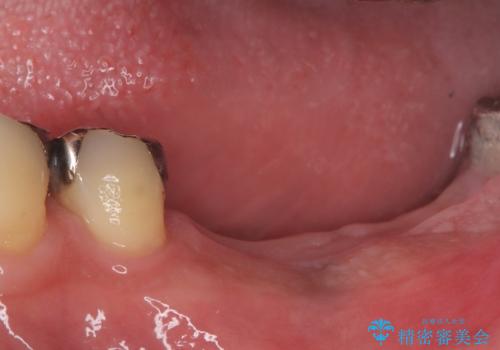

今回の治療では、まず左下6番と7番の欠損部に、骨の状態を考慮しながら慎重に2本のインプラントを埋入しました。インプラント体と骨がしっかりと結合するのを待った後、最短の期間で最終的な被せ物を装着するための精密な型取りを実施。最終的に、周囲の歯と調和した審美性の高いセラミック製の歯を装着しました。

治療期間は約3ヶ月で完了。以前の入れ歯のような煩わしさや動く心配がなくなり、天然歯と変わらない強い力でしっかりと食べ物を噛み砕けるようになり、快適な食生活を取り戻していただけました。